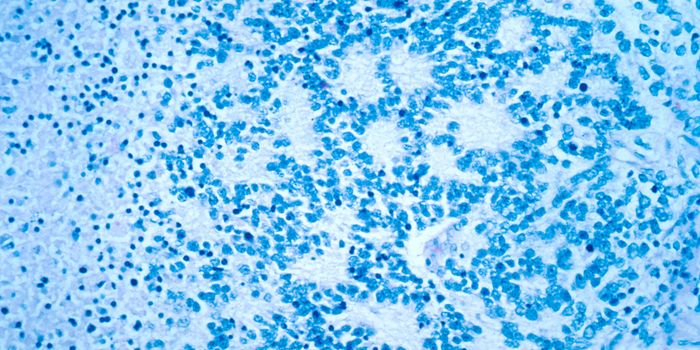

JUL 01, 2016CancerThe diagnosis of glioblastoma often bears one of the grimmest prognosis for patients. But a new research discovery may o ...

MAR 23, 2016CancerIn a large drug screening trial, scientists identified a unique drug combination that is effective against the most aggr ...

DEC 17, 2015NeuroscienceGlioblastomas or GBMs are the most devastating kind of cancer tumor found in the central nervous system in adults. Tumor ...